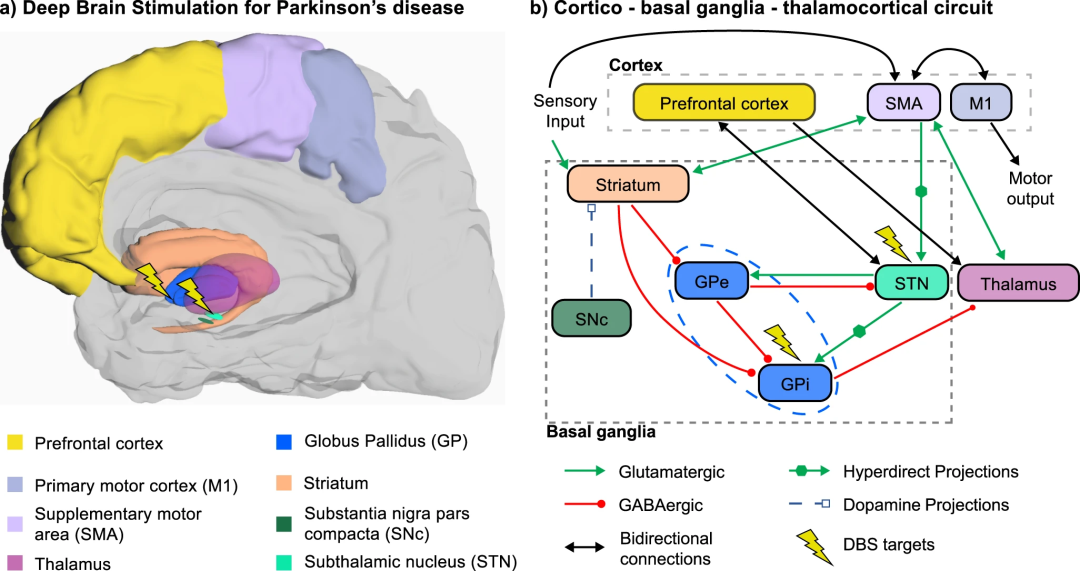

图2.帕金森病运动症状的神经调节靶点。a. BG、皮质和丘脑区参与帕金森症病理生理学的解剖位置。以STN或GPi(闪电标志)为目标的DBS是PD运动症状的主要治疗方法之一。b. PD中SNc内多巴胺能细胞的缺失会导致皮质- BG -丘脑皮质回路的直接和超直接通路的功能障碍,从而影响运动和认知功能,并且可以使用STN或GPi的DBS部分恢复。

与感觉运动神经义肢的发展同时,研究人员于1987年首次将脑深部结构电刺激(称为DBS)用于帕金森震颤,并从那时起成为几种运动障碍的主要神经调节疗法。帕金森病的特征是黑质致密部(SNc)多巴胺能神经元的进行性损失,导致一系列运动和非运动症状。运动症状主要包括震颤、肢体僵硬(强直)、运动缓慢(运动迟缓)、姿势和平衡受损。非运动症状包括自主神经功能障碍、情绪障碍和认知障碍,随着疾病的进展,从轻度认知障碍(MCI)到帕金森病痴呆(PDD)不等。PD影响整个基底神经节(BG)电路,一组皮层下区域,包括丘脑下核(STN),苍白球的外部和内部部分(GPe, GPi),纹状体和SNc。这些核通过丘脑与皮层区相互作用,从而产生几个平行的BG丘脑-皮层环(如图2)。SNc中多巴胺能细胞的缺失降低了多巴胺水平,导致BG丘脑-皮层网络活动异常,进而影响参与运动生成的运动皮层区域和参与认知功能的前额叶区域。

STN或GPi的常规DBS治疗运动症状:治疗PD相关运动症状的两种主要策略是多巴胺能药物(左旋多巴)和STN或GPi的DBS,这在两种情况下都能改善运动症状并减少所需的左旋多巴药物。传统的DBS方案采用高伽马范围(100-185 Hz)的频率,可改善运动迟缓、僵硬和颤抖,但对步态冻结和吞咽等轴向运动症状效果不佳。相反,低频DBS可以更好地控制这些症状,频率在较低的伽玛范围(60-80 Hz)。然而,传统的DBS对PD几乎没有改善,有时甚至会恶化认知功能。在一些报告中指出STN的DBS会恶化精神运动速度、记忆、语义流畅性、现象流畅性和一般认知功能。在另一项研究中,长期随访(术后3.6-10.5年)的患者表现出整体认知能力下降,并从MCI转变为痴呆,这表明传统的STN-DBS并没有阻止PD中观察到的认知能力下降。虽然关于GPi的DBS的非运动效应的文献较少,但当靶向GPi而不是STN时,认知结果似乎略好。但最近一项对91例伴有STN双侧DBS的PD患者的研究表明,STN内的精确位置本身也可能对非运动效应产生影响,包括情绪/冷漠、注意力/记忆和睡眠/疲劳,这可以解释在患者之间观察到的巨大差异。